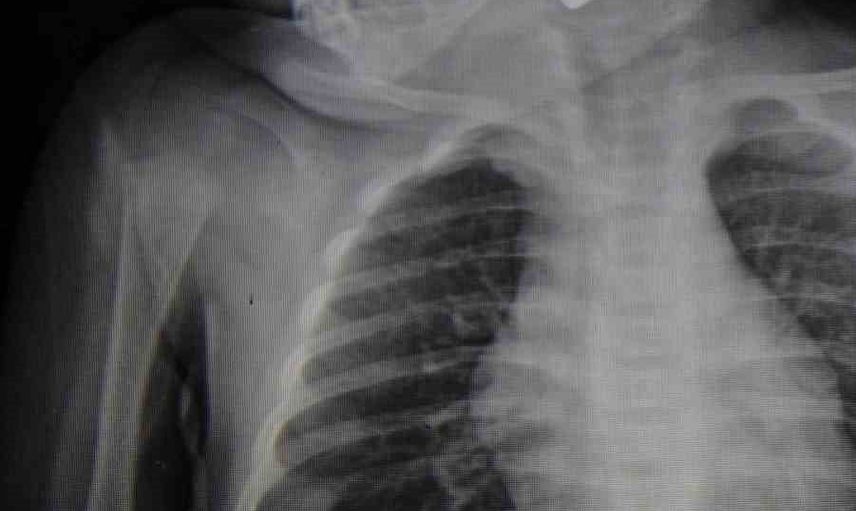

Karaman Eğitim ve Araştırma Hastanesi acil servisine kusma şikayetiyle getirilen 6 aylık E.A.'nın boğazında yapılan muayene ve tetkiklerde kumanda pili tespit edildi. Solunum sıkıntısı yaşayan bebek, Çocuk Cerrahisi Uzmanı Doç. Dr. Mehmet Uysal tarafından gerçekleştirilen ameliyatla pil çıkarıldı.

"Acil polikliniğimize kusma şikayeti ile 6 aylık bir kız bebek getirilmiş ve bize haber verildi. Biz de vakit kaybetmeden geldik, hastamızı gördük. Yapılan tetkikler sonucunda, ağız tabanına oturan ve yemek borusunun birinci darlığına kadar uzanan, kumanda pili dediğimiz bir pille karşılaştık. Filmde ve muayenede bunu gördük. Hastayı ilk gördüğümüzde bayağı siyanotik durumda, solunum sıkıntılıydı ve oksijen satürasyonu 90 civarındaydı. Böyle olunca bir an önce beklemeden hızlı bir şekilde ameliyathaneye götürdük. Orada ameliyathanedeki anestezi uzmanlarımız ve personel bize yardımcı oldu, hasta hızlı bir şekilde entübe edildi. Ondan sonra da laringoskop ve magill forseps dediğimiz malzemelerimizle bu yabancı cismi çıkarmış olduk. Bir an evvel müdahale ettik, iyi ki müdahale ettik, orada ağız tabanında, özellikle ön kısmında hasar oluşmuştu. Müdahale sonrasında da hastanın solunum problemleri bir süre devam etti, bu yüzden 24 saat takip ettik. Herhangi bir problem oluşmayınca 24 saat sonra kontrole gelmek üzere hastayı taburcu ettik" diye konuştu.